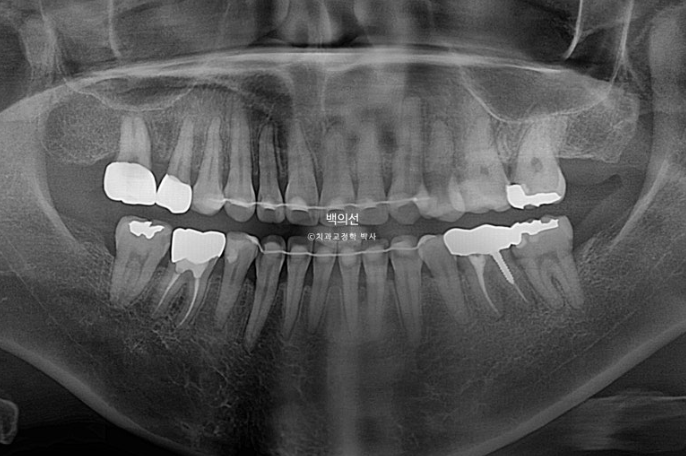

2022.12

그런데 파란 화살표 부분에 큰어금니가 하나 없습니다.

오래 전 큰어금니가 빠진 부분을 브릿지로 치료해 놓은 상태입니다.

치료의 편의성을 위해서는 작은어금니 4개 발치가 필요하나 브릿지 자체가 오래되기도 해서 파란 화살표쪽 분악은 추가적인 소구치 발치 없이 브릿지를 잘라내어 큰어금니 빈공간에 이용하기로 합니다.

그러면 작은어금니 발치갯수를 4개에서 3개로 줄일 수 뿐더라 오래전 큰어금니 빠진 자리를 임플란트 없이 교정으로 메꿀 수 있는 장점이 큽니다.

물론 단점도 있습니다. 작은어금니를 뺏을 때 생기는 7mm 정도의 공간을 줄이는 시간보다는 큰어금니가 없는 10mm이상의 공간을 줄이는 시간이 오래 걸리기에 토탈 치료기간은 통상 작은어금니 4개를 발치했을 때 걸리는 2년 보다는 몇 달 늘어나게 됩니다.

하지만 환자분께는 더 이로운 치료계획입니다. 치료의 편의성보다는 환자분에게 장기적으로 이로운 방향의 치료계획을 제시하고 있습니다.

2년 반에 걸친 교정기간동안에도 치근흡수는 없으며 치근평행도는 양호합니다.